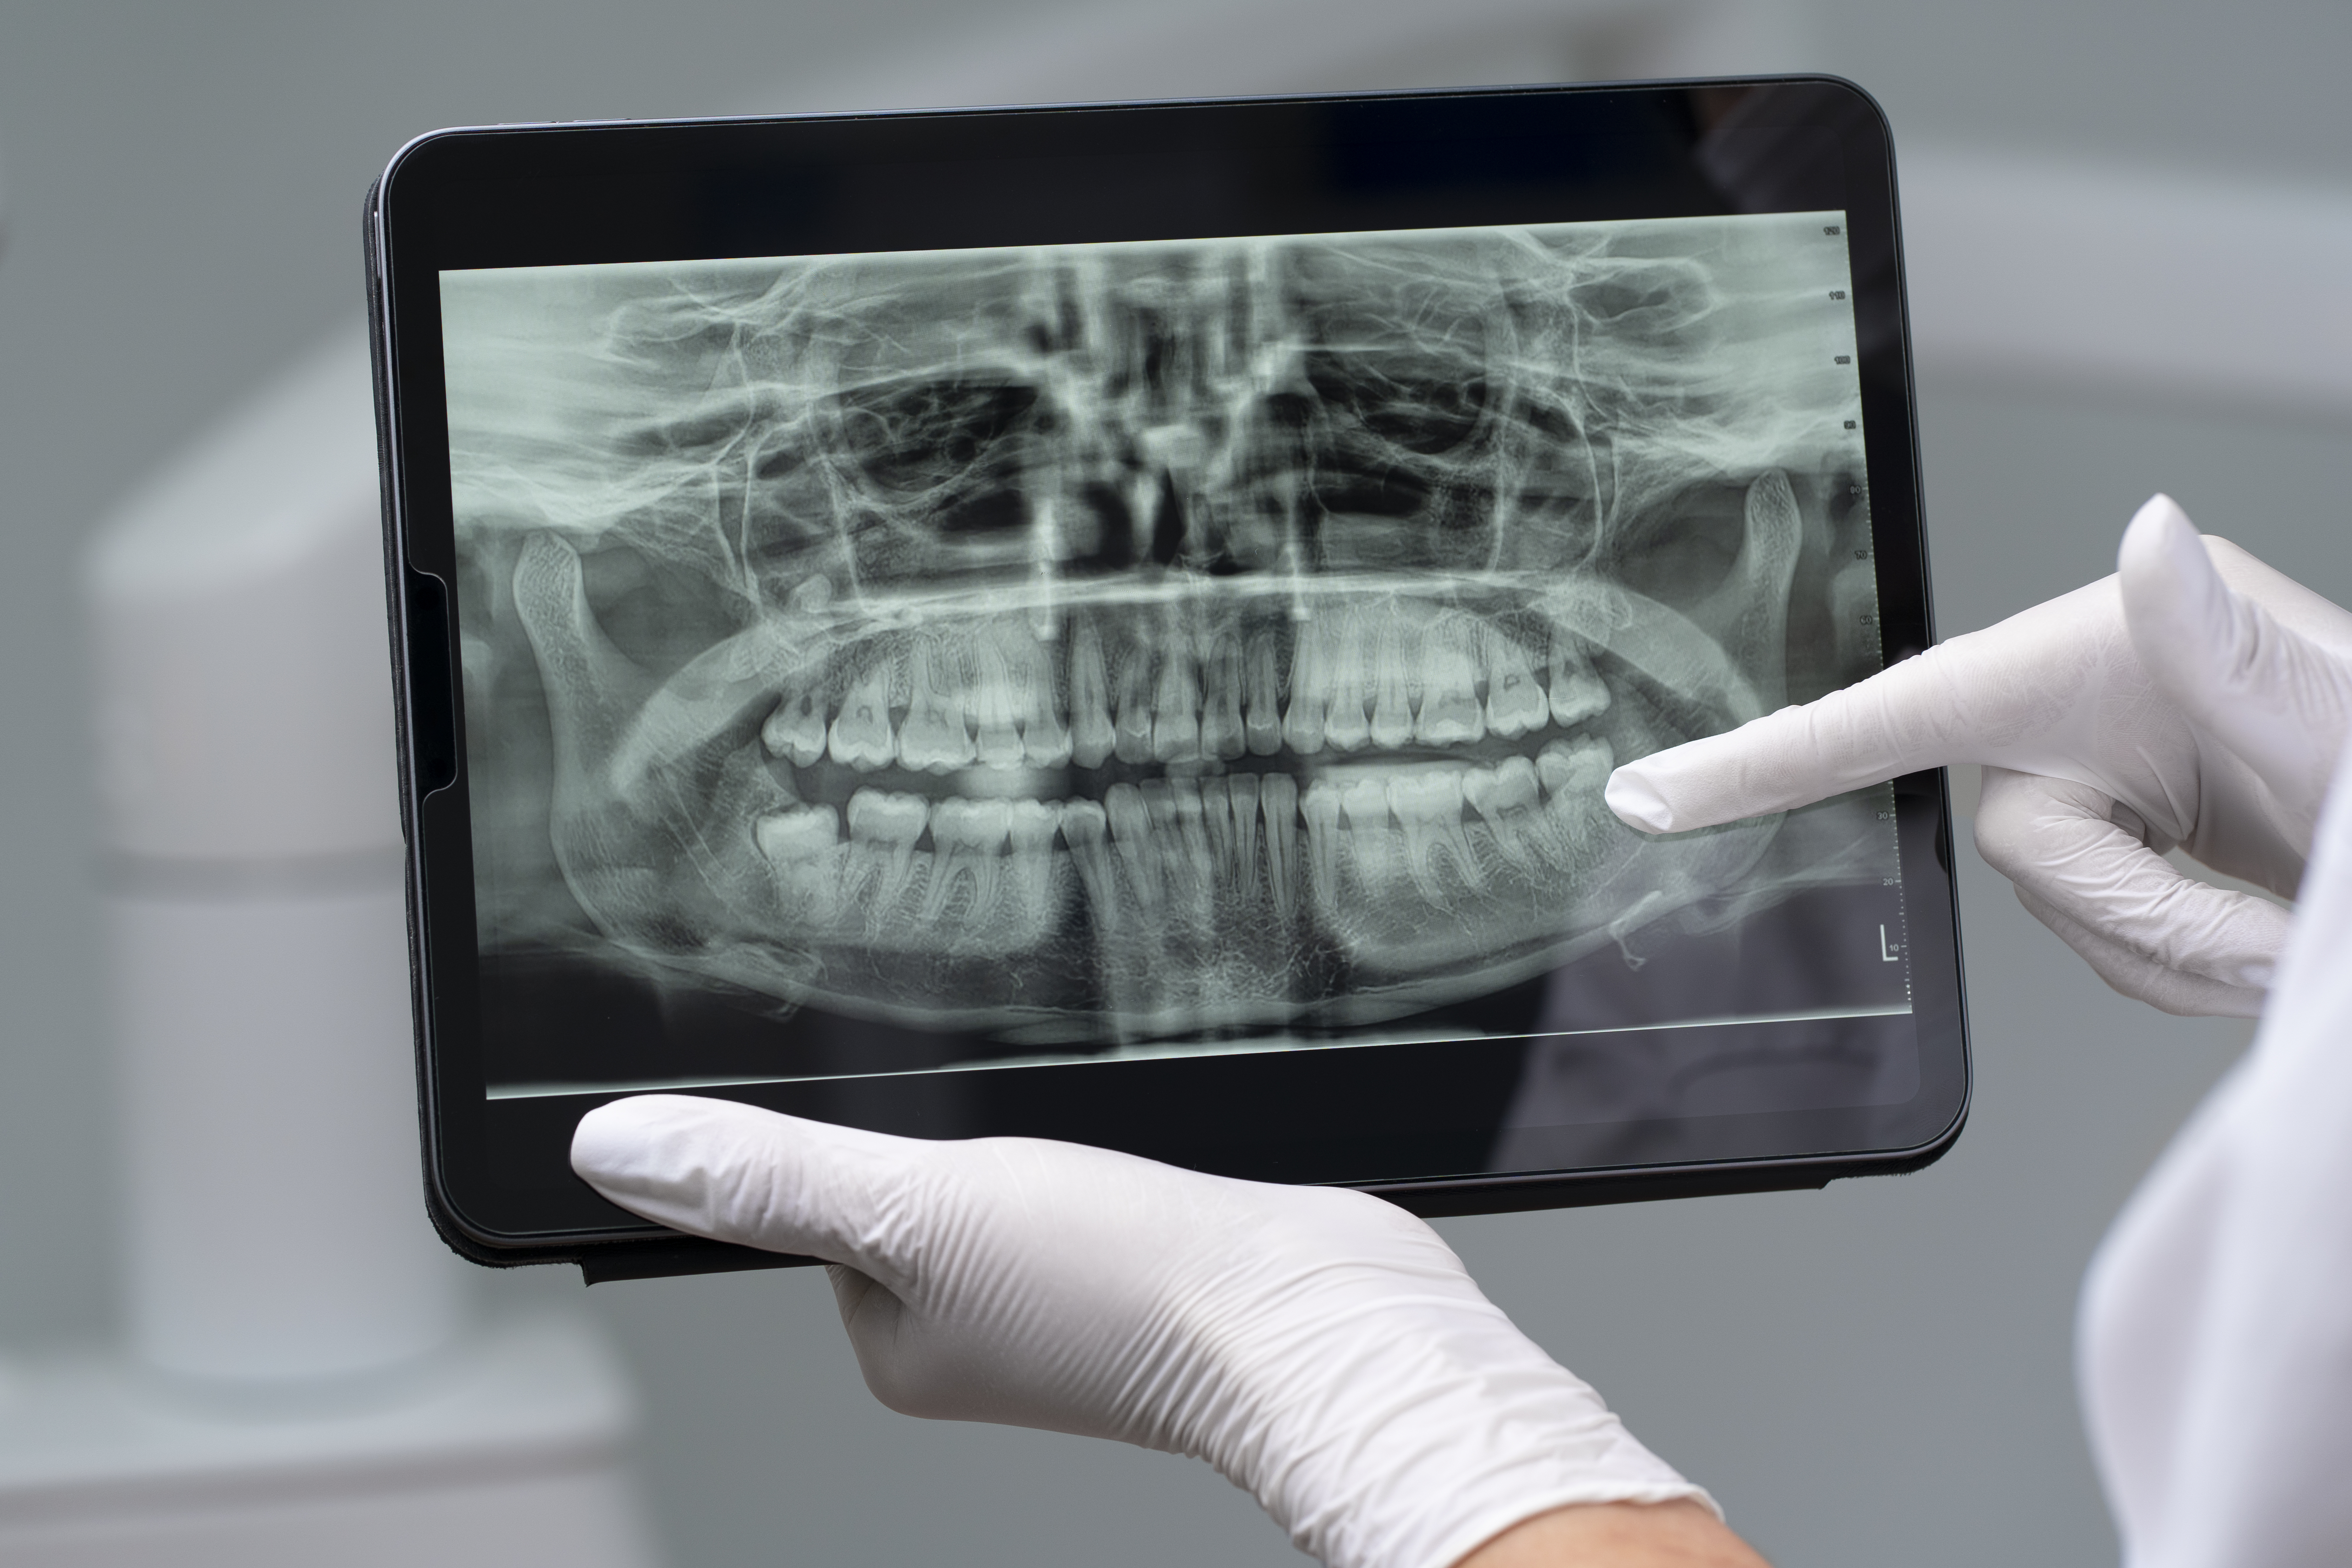

Panorâmico dentário digital

É o exame que permite ao profissional enxergar além dos dentes e oferecer um tratamento completo